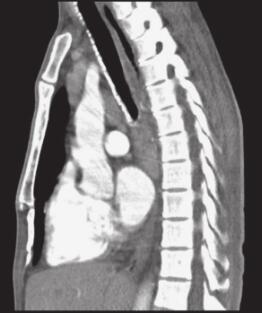

图3 肺部CT

两下肺可见片状模糊高密度影,纵隔及肺门可见多发肿大淋巴结,气管支气管软骨骨化